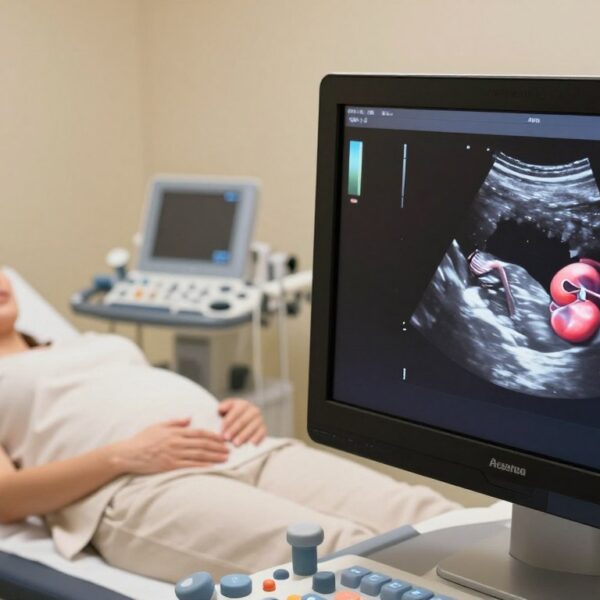

Dowiedz się więcejZdjęcia USG – jak odczytywać obraz i co warto zachować z badania

Czy wiesz, dlaczego na wydruku widzisz „plamy”, a lekarz odczytuje konkretne struktury? To pytanie otwiera nasz krótki poradnik. W…

7 tydzień ciąży USG bicie serca – kiedy zwykle jest widoczne, normy tętna i co oznacza brak

Czy to możliwe, że pierwsze sygnały życia dziecka pojawią się szybciej niż myślisz? W 6–7 tygodniu badanie obrazowe często bywa pierwszą okazją, by zobaczyć czynność serca zarodka. To też zalecany…